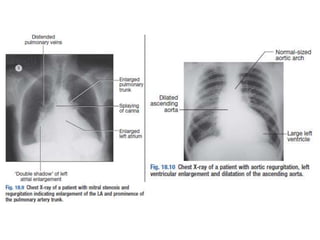

Figure 11.32 Left atrial dilatation.

This is a penetrated PA chest X-ray in a patient with mitral stenosis.

The dilated left atrium causes a bulge on the left heart border below

the pulmonary artery which is also dilated, widening of the carina

and the double density sign at the right heart border.